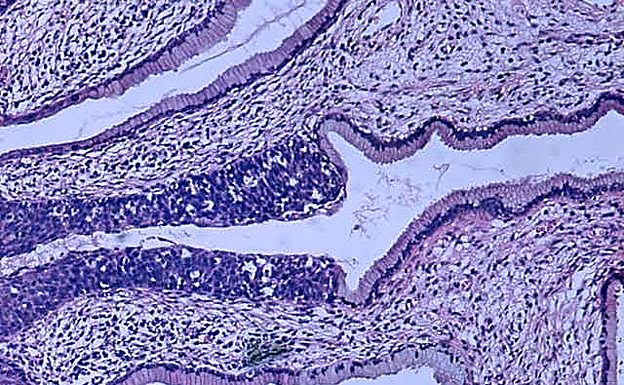

El equipo, liderado por Katsunori Tanaka, consiguió frenar el cáncer y la metástasis en ratones usando catalizadores metálicos para sintetizar fármacos anticancerígenos dentro del cuerpo de los roedores.

El procedimiento es pionero a la hora de usar la química sintética 'in vivo' con fines terapéuticos, poniendo a operar sustancias anticancerosas en lugares específicos mediante su inyección a través de una vena. Un método que permite eliminar de forma eficaz las células cancerosas y que tendría muchos menos efectos secundarios tóxicos que la tradicional quimioterapia. «Muchos pacientes mueren por los efectos secundarios. Creemos que esta tecnología podrá salvar vidas», explicaba Tanaka a 'Science Daily'.

Los investigadores han encontrado una solución que permite no introducir ningún fármaco tóxico en el cuerpo. Han conseguido fabricar anillos de benceno dentro del cuerpo, el principal elemento de la mayoría de los fármacos anticancerosos, a tavés de catalizadores de mentales de transición. Tanaka confesaba que «nadie creía que fuera posible» pero ella confiaba en poder hacerlo basándose en sus «logros anteriores».